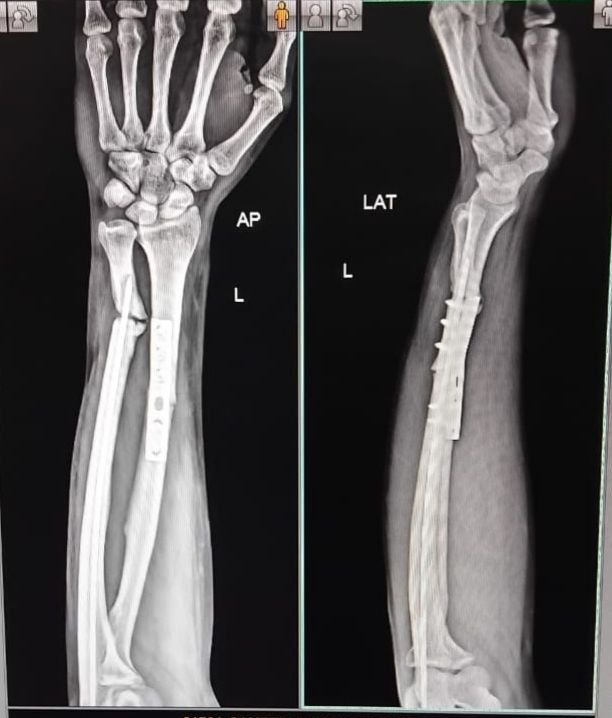

Gallery